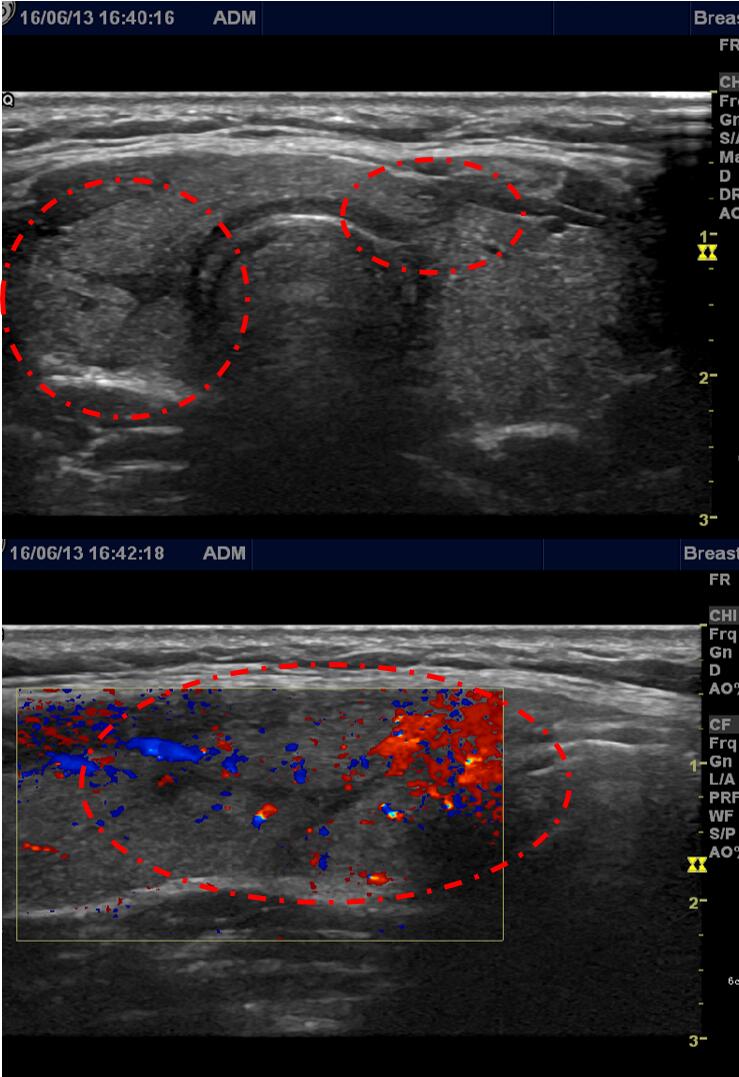

李女士微创介入消融治疗后半年(2016年6月)复查超声显示甲状腺多个消融结节吸收缩小,原消融结节位置仅看到少量消融后的痕迹(如下图)。